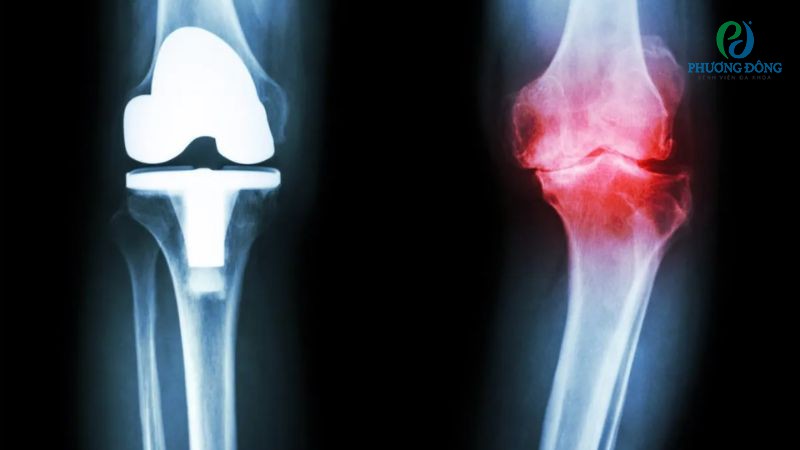

Thoái hóa khớp gối có chữa khỏi được không là thắc mắc của nhiều người bệnh. Đến nay, giới y học chưa tìm ra phương pháp chữa khỏi toàn toàn tình trạng thoái hóa khớp gối, song có thể cải thiện triệu chứng và ổn định sinh hoạt thường ngày.

Tùy theo mức độ lão hóa, bệnh nhân sẽ được chỉ định điều trị nội khoa hoặc ngoại khoa:

Thoái hóa khớp gối có thể điều trị nội khoa hoặc ngoại khoa nhưng không thể dứt điểm bệnh